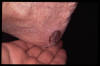

Letálides por C. de Merkel